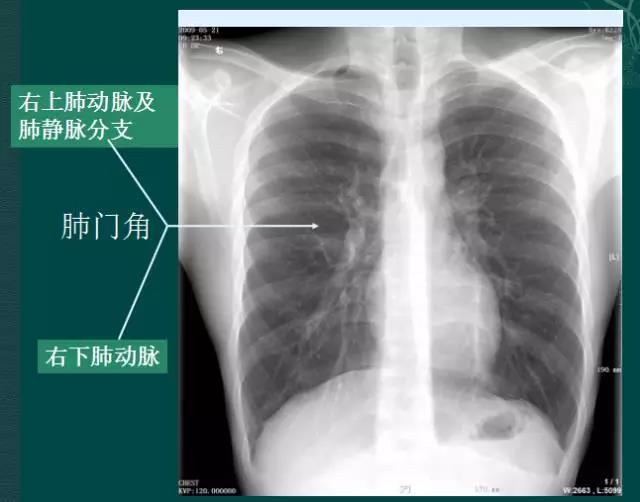

x线肺门指肺动脉、肺叶动脉、肺段动脉、伴行支气管以及肺静脉构成。

右肺门可分为上、下两部。上部约占1/3,由上肺静脉、上肺动脉及下肺动脉后回归支构成。上肺静脉下后干构成右上肺门的外缘;右肺门下部 约占2/3,由右下肺动脉干构成,其正常宽度不超过15mm,沿中间段支气管外缘平行向外下走行。右肺门上、下部相交形成一钝的夹角,称肺门角,正常该角顶清晰。如下图

左肺门亦分为上、下两部。上部由左肺动脉及其分支、左上叶支气管和左上肺静脉及其分支构成;下部由左下肺动脉及其分支构成,常被心影所遮盖。